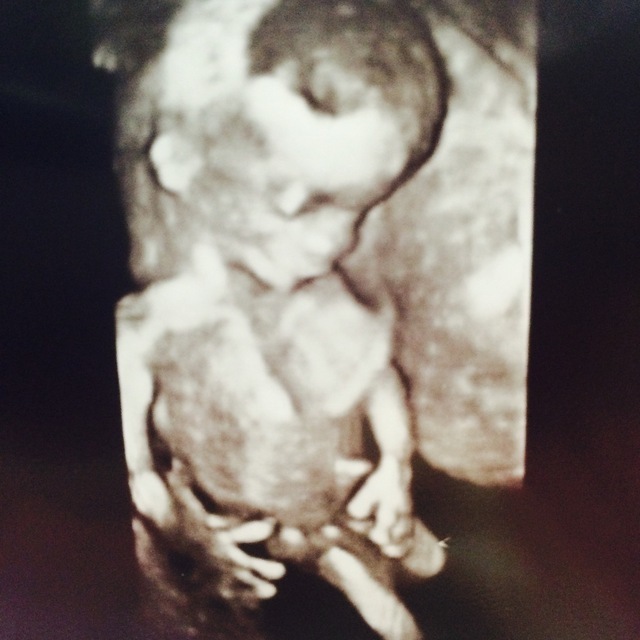

11週3日(11w3d・性別不明)|ありもん さん(27歳)

エコー写真撮影時のエピソード:

初めての腹部エコーでした。 エコーに映るとすぐに赤ちゃんが手を振ってくれていました。

お医者さんも「おてて振ってるねー赤ちゃん」と言ってくれました。 その姿が愛おしく、早くこの手で抱っこしたいと思っています。